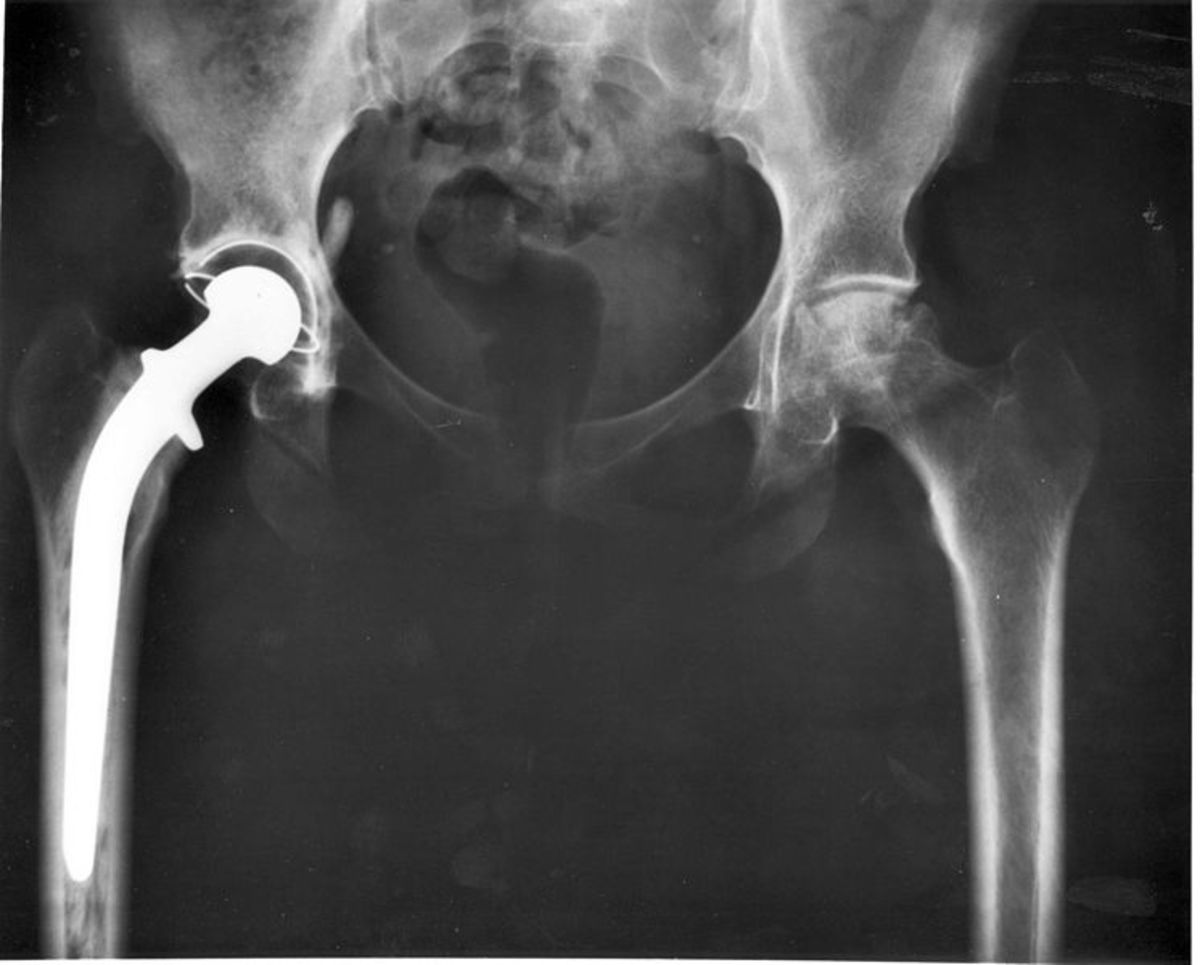

Hip Replacement Xray Radiology . Despite the widespread use of mri, ct, and sonography in joint imaging, the postoperative radiograph remains the keystone in. Total hip replacement is one of the most widely performed surgeries. This article reviews the current status of hip replacement including different types and techniques of hip replacement, various designs of hardware, standard terms in. This overview focusses on the normal findings and complications of cemented versus non. Total hip arthroplasty (tha), also known as total hip replacement (thr), is an orthopedic procedure that involves the surgical. Complications of total hip arthroplasty are common and the radiologist needs to be aware of them in the assessment of radiographs of total. Radiography is the primary imaging method for the evaluation of total hip arthroplasty. Radiography is the primary imaging method for the evaluation of hip arthroplasties, and imaging of a hip arthroplasty and its complications primarily relies on the information that is.

Complications of total hip arthroplasty are common and the radiologist needs to be aware of them in the assessment of radiographs of total. This overview focusses on the normal findings and complications of cemented versus non. Radiography is the primary imaging method for the evaluation of total hip arthroplasty. Total hip replacement is one of the most widely performed surgeries. This article reviews the current status of hip replacement including different types and techniques of hip replacement, various designs of hardware, standard terms in. Despite the widespread use of mri, ct, and sonography in joint imaging, the postoperative radiograph remains the keystone in. Total hip arthroplasty (tha), also known as total hip replacement (thr), is an orthopedic procedure that involves the surgical. Radiography is the primary imaging method for the evaluation of hip arthroplasties, and imaging of a hip arthroplasty and its complications primarily relies on the information that is.

Hip Replacement Xray Radiology Radiography is the primary imaging method for the evaluation of total hip arthroplasty. This overview focusses on the normal findings and complications of cemented versus non. Total hip arthroplasty (tha), also known as total hip replacement (thr), is an orthopedic procedure that involves the surgical. This article reviews the current status of hip replacement including different types and techniques of hip replacement, various designs of hardware, standard terms in. Radiography is the primary imaging method for the evaluation of hip arthroplasties, and imaging of a hip arthroplasty and its complications primarily relies on the information that is. Total hip replacement is one of the most widely performed surgeries. Complications of total hip arthroplasty are common and the radiologist needs to be aware of them in the assessment of radiographs of total. Radiography is the primary imaging method for the evaluation of total hip arthroplasty. Despite the widespread use of mri, ct, and sonography in joint imaging, the postoperative radiograph remains the keystone in.